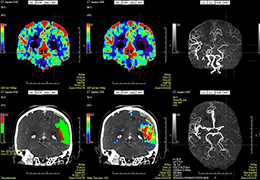

ANYTHINK 经导管主动脉瓣膜置换术分析系统